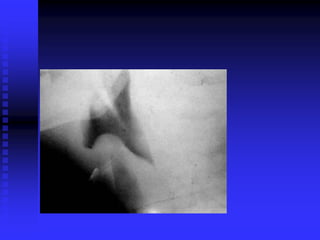

Croup X-Ray